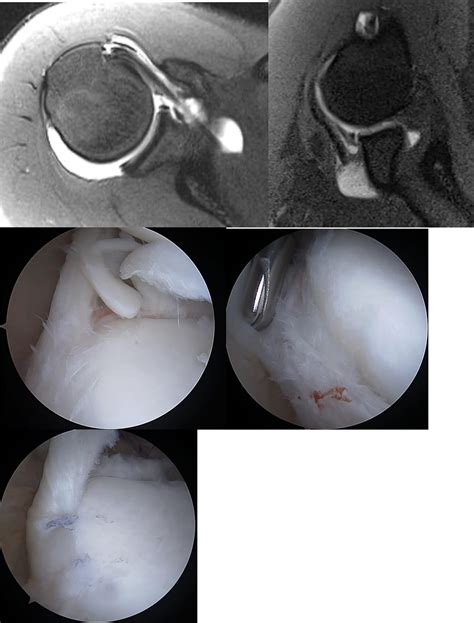

Diagnosing a Superior Labral Anterior Posterior tear can be complex because the symptoms often mimic other shoulder pathologies. Physical examinations usually involve orthopedic tests, such as the O’Brien test or the Biceps Load test, which are designed to put tension on the labrum and reproduce pain. Since clinical exams have limitations, radiologists often use Magnetic Resonance Imaging (MRI) with contrast—specifically an MRA—to visualize the tear clearly.

If physical therapy fails to restore function, or if the tear is severe (typically Type II-IV), an orthopedic surgeon may recommend arthroscopic surgery. During the procedure, the surgeon cleans out frayed edges or uses sutures and anchors to reattach the torn labrum to the bone. Recovery from this surgery requires patience and strict adherence to a physical therapy protocol to ensure the labrum heals properly to the bone.